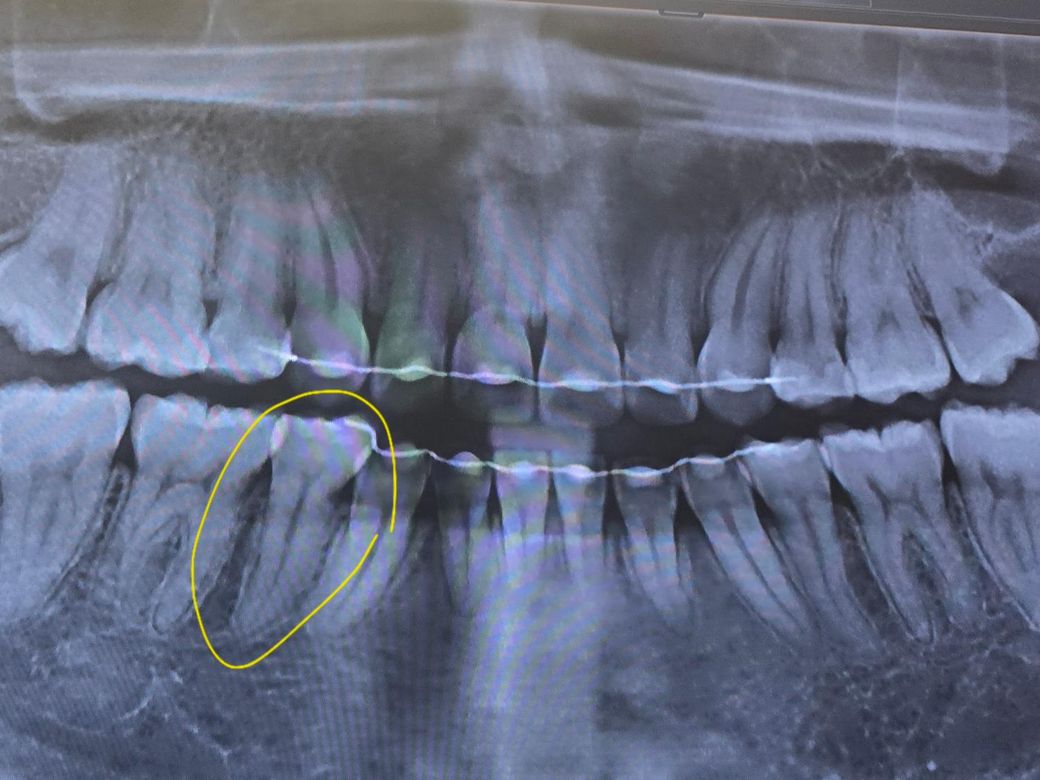

사랑니 전문 병원에서 2년전 사랑니를 빼기 전에 찍은 사진 (1) 과 2년 후에 사랑니를 빼고 나서의 사진 (2) 사이에 교정기를 단 쪽에 뭔가 파여 있는 듯 한 자국이 보이더군요... 그래서 1개월 뒤 타 치과에서 검진(3)을 받아봤는데 충치는 없다고 진단해주셨습니다... 원래도 시림 증상도 없고 멀쩡해서 안심이긴 하지만 타 선생님이 보시기에도 충치가 아닌지 궁금합니다 ㅜ 점점 신경 쪽하고 가까워지고 있는 것 같기도 해서요...🥺

파노라마 엑스레이는 다양한 왜곡, 음영이 있어서 판단이 어렵고요 충치 의심 부위에 치근단 엑스레이를 찍어봐야합니다

사진으로 보이는 부위는 방사선사진이 어둡게 보이는 곳입니다. 인접면의 충치를 정확하게 판단하기 위해서는 치근단사진이나 육안검사가 필요할 것으로 생각됩니다.

방사선 사진에는 치경부 소환 이라는 것이 있는데요 말씀하신 치아의 목 부위(머리와 뿌리 사이)가 다른 곳 보다 더 까맣게 보이는 것입니다. 일종의 착시현상같이 저렇게 보이는 것인데 사진을 찍을때마다 심하기도, 정상으로 보이기도 합니다. 육안으로 봤을때 괜찮고 증상이 없으시다면 크게 걱정하지는 않으셔도 되겠습니다.

사진상으로는 충치가 깊어 보이거나 그렇진 않습니다. 지금처럼 관리를 잘하시면될것같습니다.

사진의 선명도에 따라 달라보일 수 있지만 가능성이 보입니다. 치과에서 해당 치아 문의해보시면 좋겠습니다.